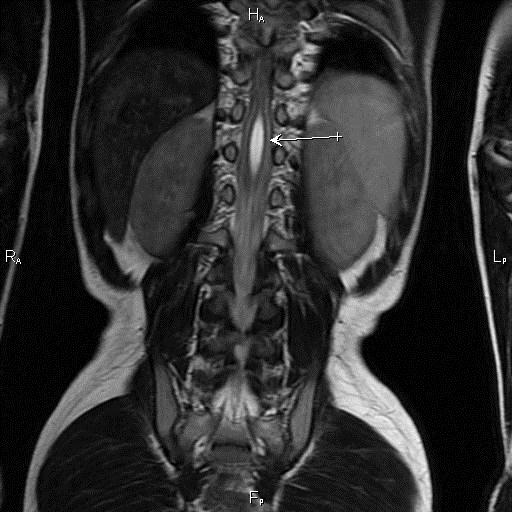

Для исключения других состояний, таких как эпилепсия или новообразования головного мозга, врач может назначить электроэнцефалограмму (ЭЭГ) или магнитно-резонансную томографию (МРТ). В большинстве случаев при ДПГД результаты этих исследований будут в пределах нормы.